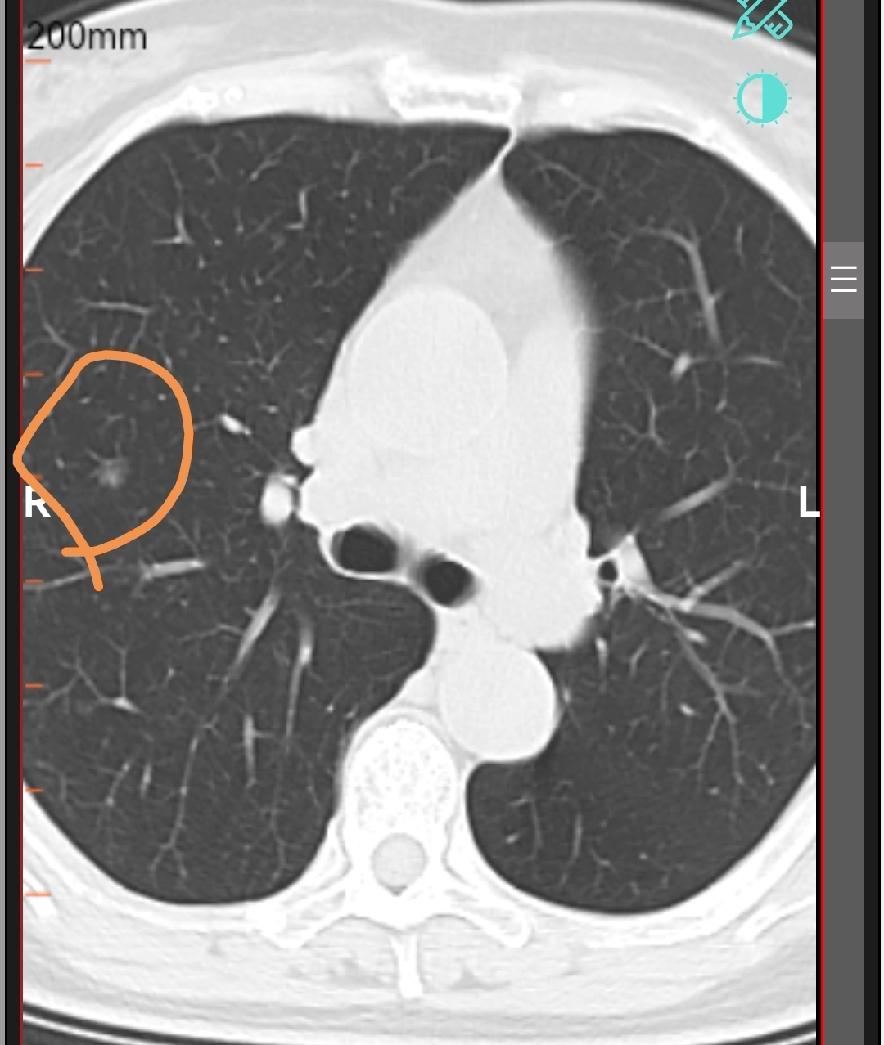

肺结节报告3个关键指标!你都知道吗?